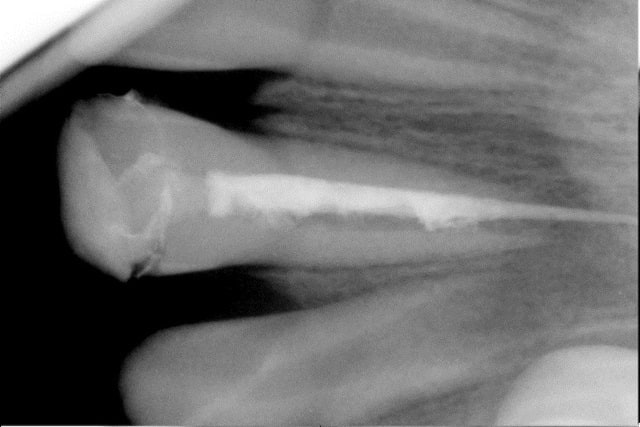

Gamin de 8 ans, fracture de sa 21 suie a trauma..

Vu en urgence..Pulpectomie, mise en place d'hydroxide de calcium..explications,certificat,..

Revu 15 jours apres..Hydroxide de calcium de nouveau..

3 semaine plutard (5 semaines après trauma)..Tentative d'endo..le gamin qui pleure, qui bouge etc...Finalement un gros dépassement...

y a un cone , et on voit que le canal n'est pas rempli